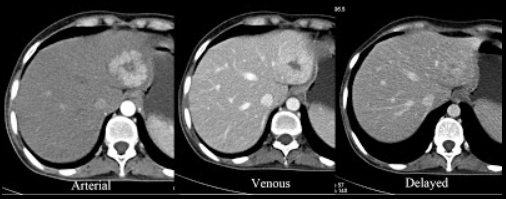

These two modalities are used to determine clinical T stage.

MRI

ERUS